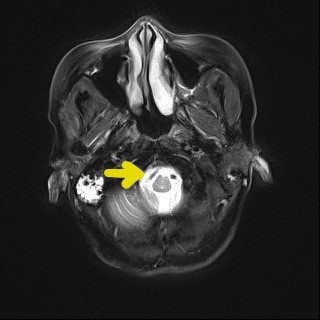

入院后主管医生为任女士完善了桥小脑角区磁共振成像,提示任女士右侧三叉神经和舌咽神经受压。颅神经就像电线,一旦受到血管异常的压迫,就会出现“短路现象”,受压部位异常放电,导致患者出现疼痛症状。要想解决这个问题,最根本的办法还是通过手术治疗,在术中通过特殊的隔离材料,将责任血管和受压的颅神经分离开来,最终彻底解除患者疼痛。

(桥小脑角磁共振显示责任血管压迫神经)